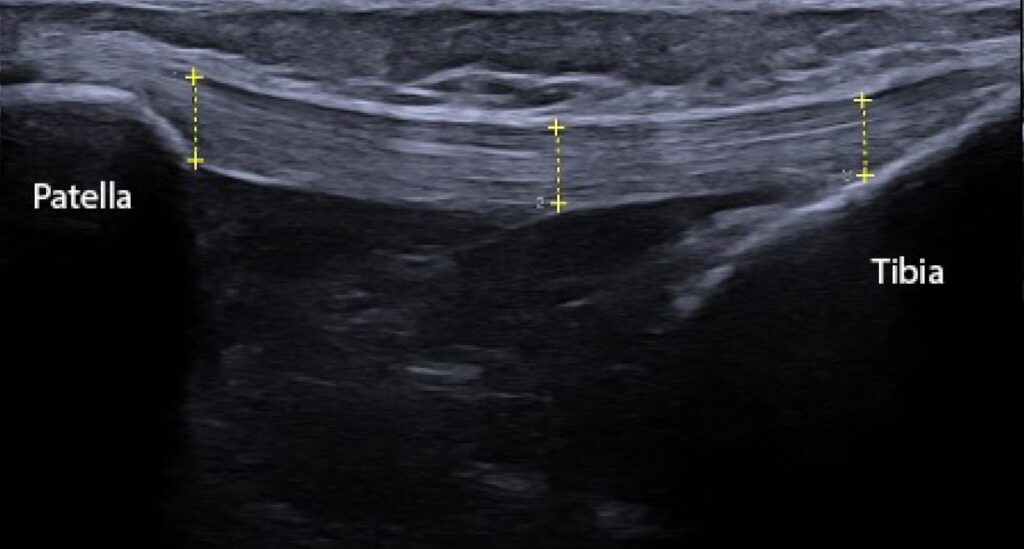

Figure 2: Ultrasound image (ACUSON Redwood Ultrasound System, Siemens Medical Solutions USA, Inc., Issaquah, WA) of the length of the patellar tendon. There are 3 locations where clinicians may choose to measure the thickness of the patellar tendon (proximal, middle, distal). Thickening of the tendon is a common pathological sequalae of patellar tendinopathy, particularly at the inferior pole of the patella.

Tendon thickness, meanwhile, may provide more information regarding the condition of the tendon that is clinically relevant. Pathological tendons present with tissue disorganization, which manifests upon evaluation and imaging as a thicker tendon compared to healthy tendons.11 In addition, scanning the entire length of the patellar tendon may yield differences along the continuum of the patellar tendon, for example at the origin at the inferior pole of the patella or the insertion at the tibial tuberosity (Figure 2). One study that evaluated patellar tendons in athletes found that the proximal patellar tendon was significantly thicker in those with patellar tendinopathy.12 While another study evaluated patellar tendons in beach volleyball players and noted that individuals with no tendinosis had an average patellar tendon thickness of 4.7/4.8 mm (dominant vs non-dominant knee) while symptomatic athletes demonstrated an average thickness of 7.6/7.0 mm( P <0.001 for dominant knee; P = 0.001 for non-dominant knee).13 Therefore thickness may be an important metric for clinicians to capture.